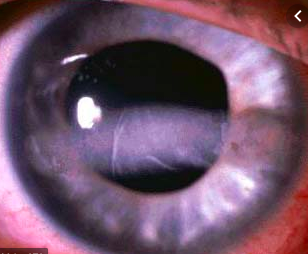

Band Keratopathy